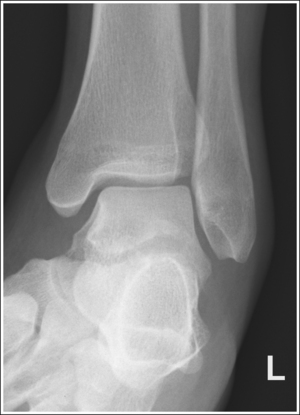

See Figure 6-46 and Box 6-10.

The ankle is demonstrated in an AP projection. The medial mortise (tibiotalar articulation) is open, and the distal tibia and talus are superimposed over the distal fibula by a small amount (0.125 inch [3 mm]), closing the lateral mortise (fibulotalar articulation).

• An AP projection of the ankle is obtained by positioning the patient supine on the image table, with the leg fully extended and the foot dorsiflexed until its long axis is placed in a vertical position (Figure 6-47). In this position, the intermalleolar line (imaginary line drawn between the medial and lateral malleoli) is at a 15- to 20-degree angle with the IR. The medial malleolus is positioned farther from the IR than the lateral malleolus.

• Detecting direction of ankle rotation. If the ankle was not positioned in an AP projection but is rotated laterally or medially, the medial mortise is obscured. When an AP ankle projection demonstrates a closed medial mortise, one can determine which way the patient's leg was rotated by evaluating the amount of tibia and talar superimposition of the fibula and the position of the medial malleolus. In external rotation, the tibia and talus demonstrate greater superimposition of the fibula and the posterior aspect of the medial malleolus (Figure 6-48) is situated medial to the anterior aspect (see Image 32). In internal rotation, the fibula is demonstrated without talar superimposition (see Image 33).